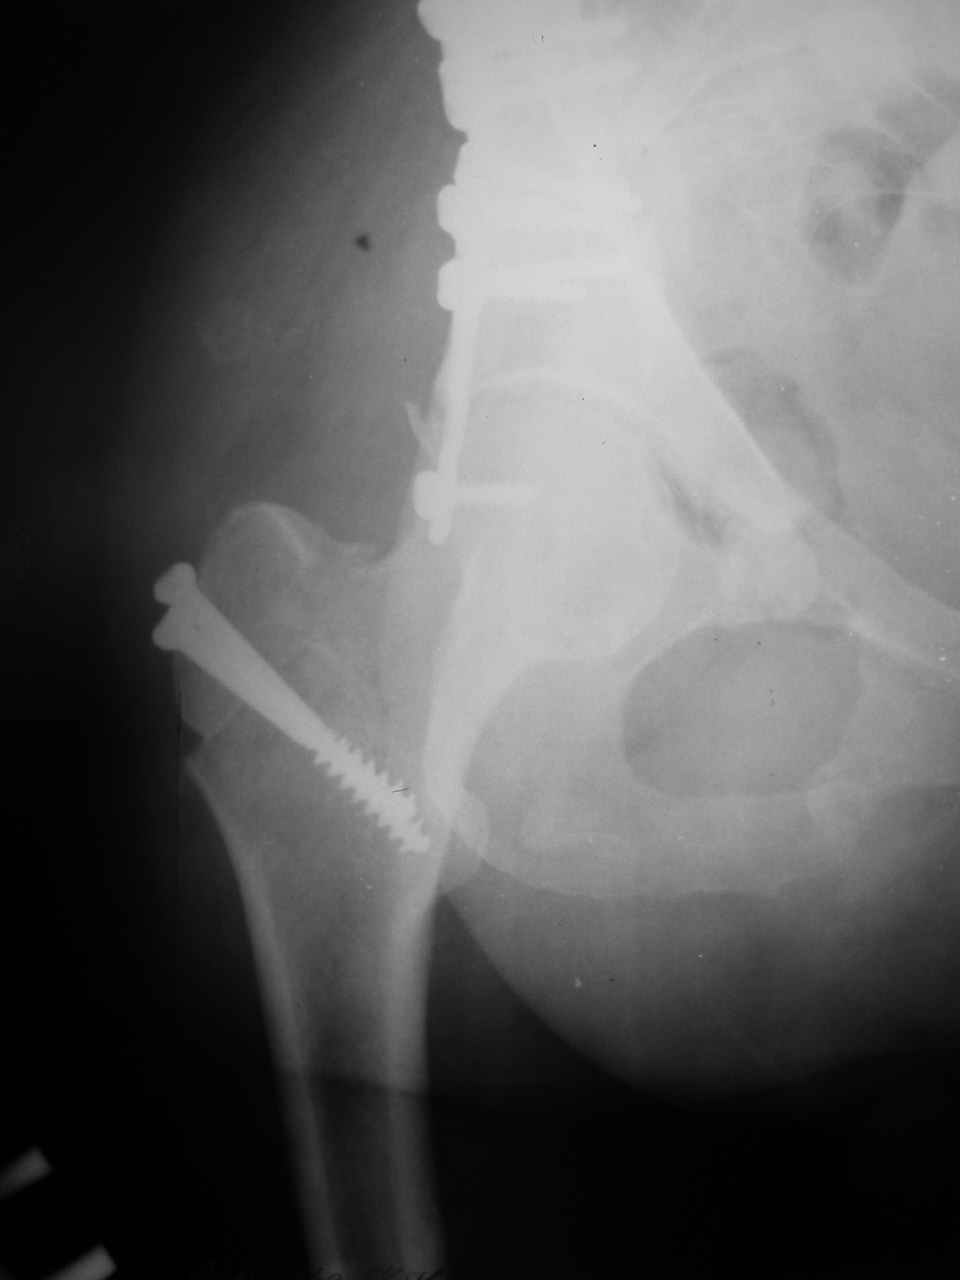

Спасибо за комментарии и рекомендации. Откровенно говоря, больного я прооперировал на прошлой неделе, через 5 дней после аварии и проблем с ним пока никаких нет, на удивление при достаточно обширной диссекции (илиофеморальный доступ) болей практически нет, так что больной самостоятельно садится в кровати, выполняет активные движения в оперированном суставе, сгибая до 60 градусов пока, далее с ассистенцией.

Причиной обращения к сообществу были возникшие непосредственно после операции сомнения и разочарования полученным качеством репозиции: а надо ли было трогать перелом вообще, репозиция передней колонны технически была очень сложна для меня, хотя реконструкции была в той же последовательности, что Д-р А.В.Рунков рекомендовал, в какой-то момент безуспешных манипуляций стал думать о *вторичной конгруэнтности*, которую не так давно обсуждали на

форуме и скелетном вытяжении. С репозицией и фиксацией задней колонны и отдельно задне-верхней стенки впадины проблем не возникло. Послеоп. Рг граммы в приложении. Если возникнут какие-либо дополнения или поправки - был бы признателен.

А какой отдел вертлужной впадины более важен передний или задний? Чем был обусловлен выбор доступа к суставу? Проще говоря, почему вы пошли передним доступом на двухколонный перелом? Мне понятны ваши сомнения, когда не удется сделать все что хотелось бы. В данном случае доступ должен быть чрезвертельным боковым (как и советовал Рунков) или двумя доступами.

> передним доступом на двухколонный перелом?

Илеофеморальный доступ не совсем передний и сравнительно с илеоингвинальным, и Кохера-Лангенбека открывает весь наружный таз кроме самых передних отделов лонных костей, фиксацию которых я не ставил в задачу. Обширность диссекции, большая длительность операции и более высокий риск гетерооссификации - отрицательные моменты в обмен на возможность легче ориентироваться.